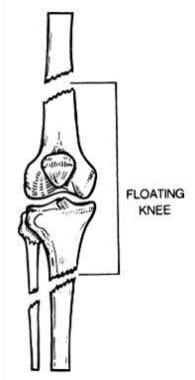

Luxating patella Wikipedia best sale, Floating Knee Physiopedia best sale, Kneecap Instability Medial vs Lateral Patellar Dislocation best sale, Floating Knee Cap recurrent patellar dislocation knee cap Flickr best sale, Floating Knee What Is Floating Knee best sale, Luxating patella in dogs PDSA best sale, Patella Slipping Knee shellylildoggrooming best sale, The Story of the Floating Knees Sanna Dyker best sale, Surgery and non surgical treatments for chronic knee cap best sale, Floating knee A modified Fraser s classification and the results best sale, PDF Bifocal disruption of the knee extensor apparatus best sale, Fraser s classification of floating knee. Download Scientific best sale, Patellar Luxation a Painful Preventable Problem for Small Dogs best sale, Kneecap Instability Medial vs Lateral Patellar Dislocation best sale, Floating Knee Practice Essentials Pathophysiology Etiology best sale, Floating Knee PDF best sale, Patellar Instability Knee Sports Orthobullets best sale, Luxating Patella in Dogs Knee Dislocation Symptoms Causes best sale, Floating Knee Practice Essentials Pathophysiology Etiology best sale, Knee Pain Can Physiotherapy Help The Physio Lounge Blog best sale, Patellar Dislocations Everything You Need To Know Dr. Nabil Ebraheim best sale, Chondromalacia Harvard Health best sale, Kneecap Instability Medial vs Lateral Patellar Dislocation best sale, Frontiers The current issues and challenges in the management of best sale, Patella Kneecap Anatomy and Function best sale, Luxating Patella in Dogs best sale, Floating Knee PDF best sale, Patellar Fractures Broken Kneecap OrthoInfo AAOS best sale, Management of the Floating Knee in Polytrauma Patients best sale, Luxating Patella in Dogs A Complete Guide Dr. Buzby s ToeGrips best sale, Floating Knee Practice Essentials Pathophysiology Etiology best sale, Luxating Patella in Dogs Signs Surgery Cost More Pawlicy Advisor best sale, ii The floating knee in adults and children ScienceDirect best sale, Patellofemoral Instability Kneecap Knee Joint Problems best sale, Patellar Instability symptoms causes best treatment best sale.